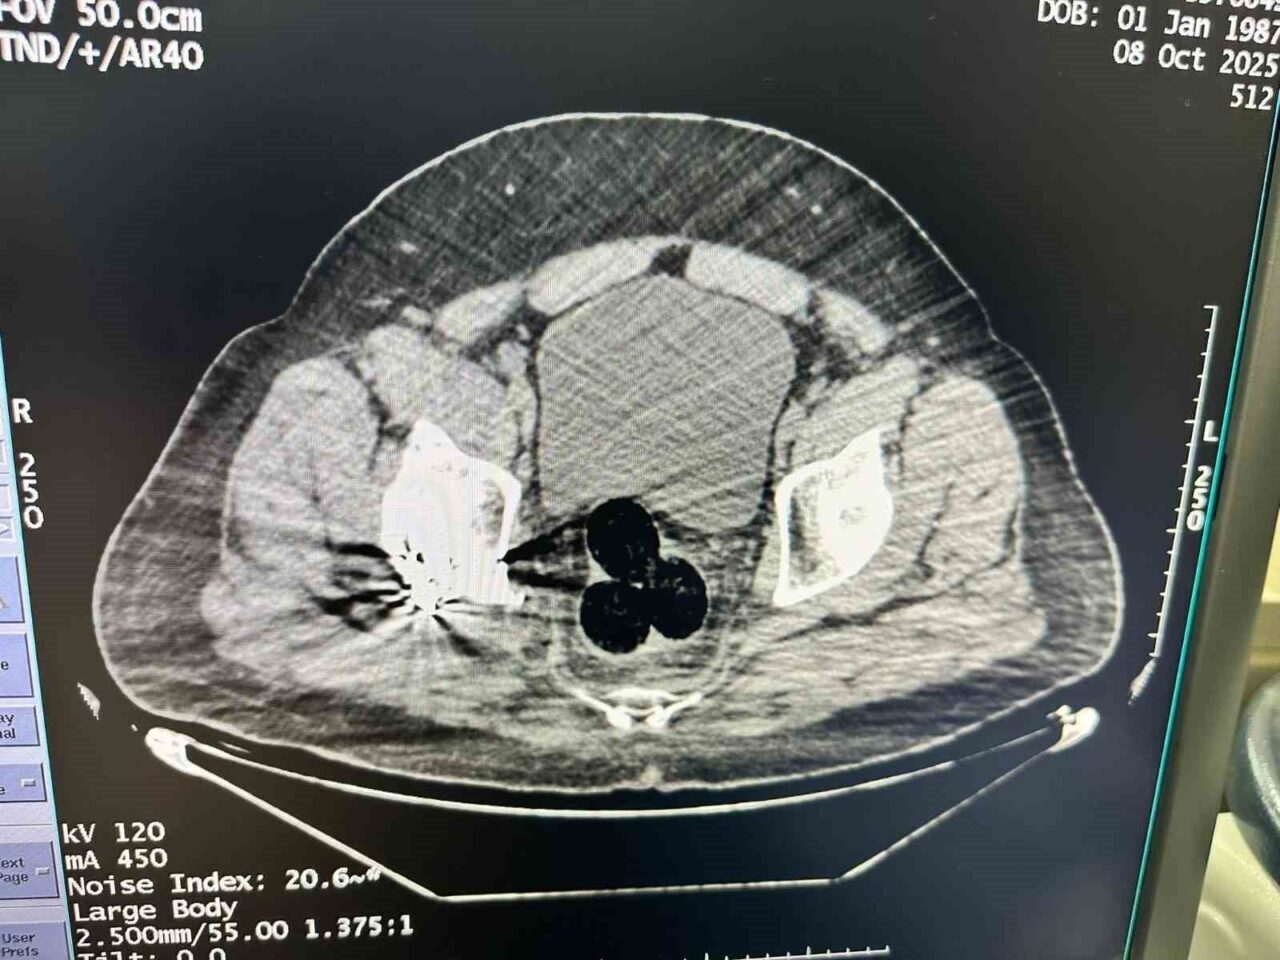

Alınan bilgilere göre, Iğdır İl Emniyet Müdürlüğü Narkotik Suçlarla Mücadele Şube Müdürlüğü, İran’dan yasa dışı yollarla ülkeye giriş yapan bir şahsı şüphelenerek takibe aldı. Gözaltına alınan bu kişi, uyuşturucu madde bulguları tespit edilmesi amacıyla hastaneye sevk edildi. Muayenede, şüphelinin makat bölgelerinde üç adet yabancı cisim belirlendi.

Yapılan cerrahi müdahale sonucunda çıkarılan paketin içinde toplamda 130 gram metamfetamin bulundu. Gözaltına alınan şüpheli, emniyet güçleri tarafından sorguya alındı. Ayrıca, uyuşturucunun kentte dağıtımını yaptığı değerlendirilen iki kişi daha yakalandı. Bu kişilerin üzerinde ve adreslerinde gerçekleştirilen aramalarda ek olarak 47 gram metamfetamin daha ele geçirildi.